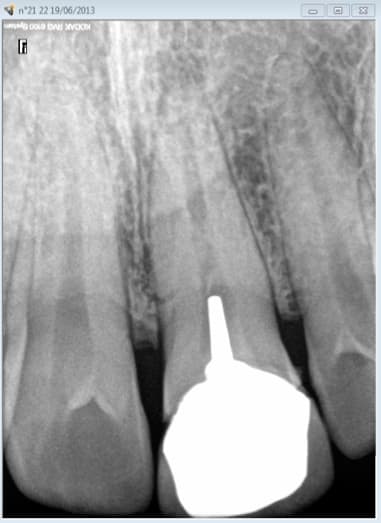

cette 21 est conforme aux recommandations radiologiquement ?

Et toutes les couronnes acceptées à l'epoque des DEP sur des endos foireuses étaient conformes radiologiquement ?

Qu'est ce que tu appelles conforme radiologiquement ? Le fait de ne pas avoir de pèche à l'apex le jour de la réalisation de l'endo ? -)

Dites moi dans votre consultation là. Mais il manque les radios recommandées par la HAS.

Examen incomplet : Indu. -)

Tu peux mettre la radio en fichier téléchargeable que je te fasse l’endos sur cette dent. Voir, tant qu'on y est, je traite en même temps la lésion apicale.

J'ai fait le RTE. mais je n'ai pas la technique pour traiter la lésion. Faut que je me forme. -)

Pour etre complet il faudrait refaire la couronne aussi. -)